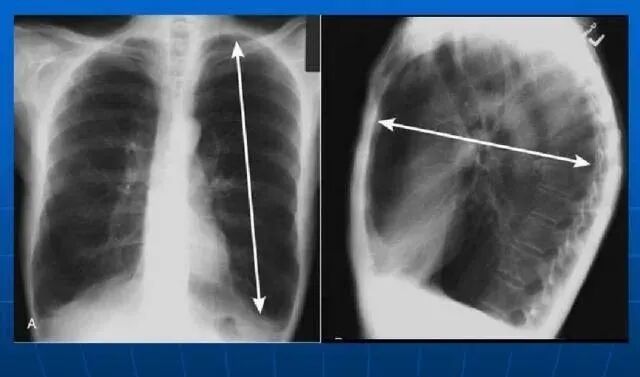

慢性阻塞性肺病的确切病因不清楚,一般认为与慢支和阻塞性肺气肿发生有关的因素都可能参与慢性阻塞性肺病的发病。已经发现的危险因素大致可以分为外因(即环境因素)与内因(即个体易患因素)两类。外因包括吸烟、粉尘和化学物质的吸入、空气污染、呼吸道感染及社会经济地位较低的人群(可能与室内和室外空气污染、居室拥挤、营养较差及其他与社会经济地位较低相关联的因素有关)。内因包括遗传因素、气道反应性增高、在怀孕期、新生儿期、婴儿期或儿童期由各种原因导致肺发育或生长不良的个体。慢性阻塞性肺疾病患者会根据病情的严重程度出现不同程度的肺功能下降。肺功能下降的症状包括胸闷、喘息、呼吸困难和气短等

如果肺功能进一步降低,肺通气量潮气量进一步降低和下降,那么不仅会出现缺氧问题,还会出现二氧化碳滞留问题。这一阶段称为“II呼吸衰竭”。在这个阶段,病人的小气道严重阻塞,气体交换困难。在这个阶段,单靠吸氧并不能解决所有问题。由于通气不足很容易将二氧化碳留在体内,因此在这个阶段有必要使用呼吸机来增加二氧化碳排放。